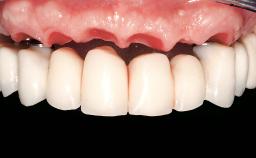

Immediate Loading of Six Implants in the Maxilla and Final Restoration with a Full-Arch Gold/Ceramic FDP Involving the Concept of Tilted Implants

A 61-year-old male patient with a failing fixed maxillary rehabilitation and a fixed mandibular rehabilitation requested a new fixed maxillary rehabilitation. The patient was wearing a temporary metal-reinforced maxillary bridge inserted two years before the consultation. He reported that his previous dentist did not want to insert a definitive framework because he considered the residual teeth to have a negative prognosis. The patient reported a history of recurrent caries and endodontic complications as the main reason for the previous extractions. The anamnesis was negative for periodontal disease and bruxism. The patient’s chief compliant was the mobility of his maxillary prosthesis, which needed to be re-cemented frequently, and discomfort during chewing.Moreover, the patient was not satisfied with the esthetic appearance of his maxillary teeth, which he found too long. The patient asked for a stable and comfortable fixed maxillary rehabilitation and firmly rejected any removable solution.

Prosthesis Type FDP

Retention Cemented, with prosthesis margin < 3mm submucosal Cemented, with prosthesis margin < 3mm submucosal

Provisional Implant-Supported Prosthesis Prosthodontic margin < 3 mm apical to mucosal crest Prosthodontic margin < 3 mm apical to mucosal crest